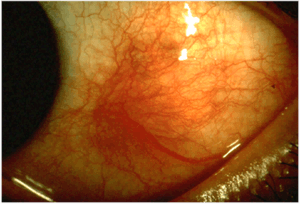

Scleritis is a serious inflammatory disease that affects the white outer coating of the eye, known as the sclera. The disease is often contracted through association with other diseases of the body, such as granulomatosis with polyangiitis or rheumatoid arthritis. There are three types of scleritis: diffuse scleritis (the most common), nodular scleritis, and necrotizing scleritis (the most severe). Scleritis may be the first symptom of onset of connective tissue disease.[1]

- Redness of the sclera and conjunctiva, sometimes changing to a purple hue

The pain of episcleritis is less severe than in scleritis.[4] In hyperemia, there is a visible increase in the blood flow to the sclera (hyperaemia), which accounts for the redness of the eye. Unlike in conjunctivitis, this redness will not move with gentle pressure to the conjunctiva.

Scleritis is best detected by examining the sclera in daylight; retracting the lids helps determine the extent of involvement. Other aspects of the eye exam (i.e. visual acuity testing, slit lamp examination, etc.) may be normal. Scleritis may be differentiated from episcleritis by using phenylephrine or neosynephrine eye drops, which causes blanching of the blood vessels in episcleritis, but not in scleritis.[4]